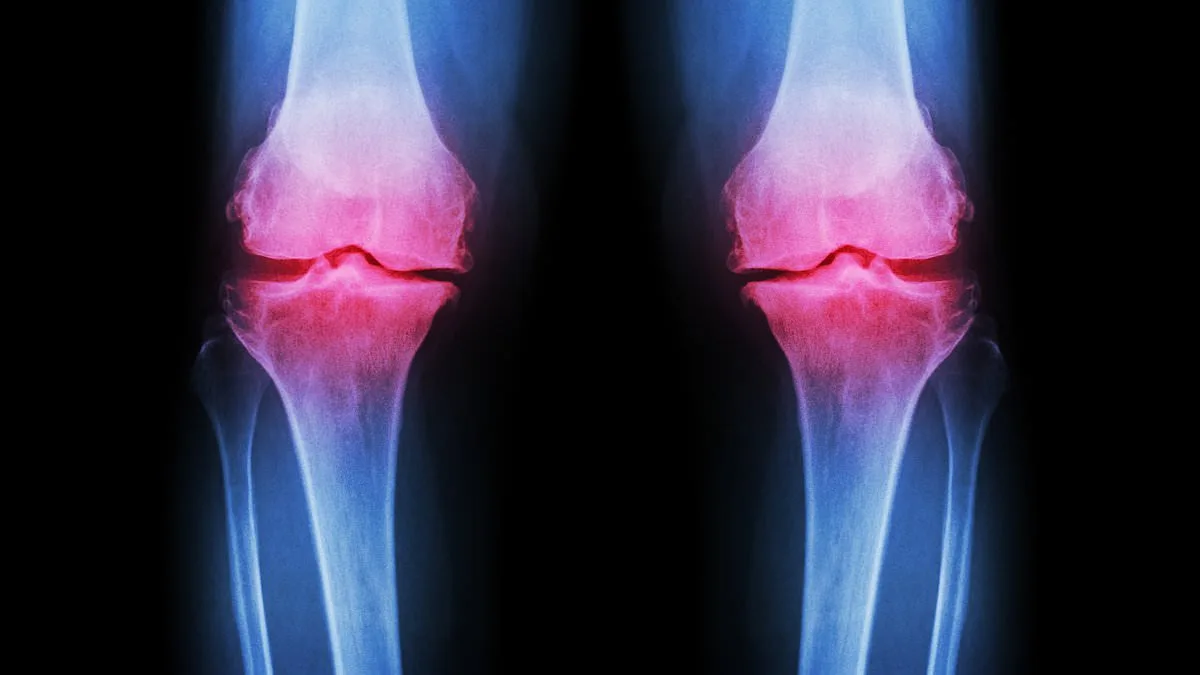

Osteoarthritis, a condition affecting millions globally, is typically associated with aging. Yet, its presence is now being diagnosed in younger populations at an unprecedented rate. By the age of 70, roughly half of all individuals will develop arthritis, but experts warn that the trend is shifting. In the UK alone, around 10 million people live with osteoarthritis, and younger generations are increasingly being affected. The condition arises when the cartilage that cushions joints deteriorates, leading to pain, stiffness, and mobility issues. While factors like genetics, obesity, and injury contribute to this decline, the role of extreme exercise and poor dietary habits in accelerating the process cannot be overlooked.

Post-traumatic osteoarthritis, a subset of the condition, often results from fractures that extend into joints. These injuries can disrupt normal joint mechanics, causing cartilage to break down more rapidly. However, unlike osteoporosis—where fragile bones significantly increase fracture risk—osteoarthritis can be mitigated through lifestyle adjustments. The challenge lies in the fact that many young people remain unaware that their exercise and diet choices can exacerbate their risk. For instance, the exclusion of dairy products in 'clean eating' diets is leading to calcium deficiencies, which weaken bones and increase inflammation.